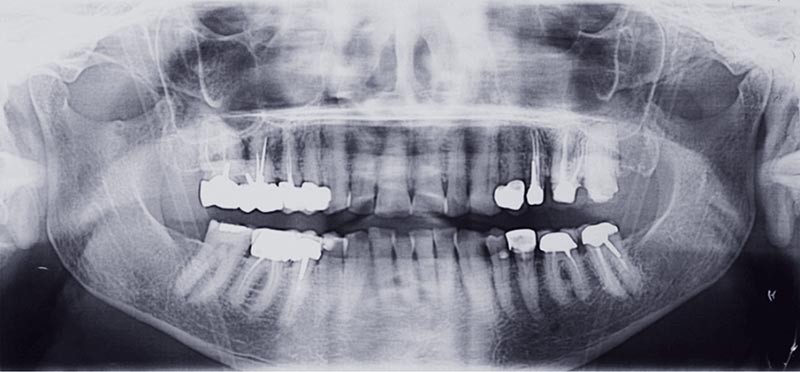

Connaître les tableaux cliniques associés aux douleurs neuropathiques et idiopathiques permet d’éviter les actes inutiles. L’identification diagnostique est plus facile quand les dents sont indemnes et exemptes de lésions. La qualité des traitements endodontiques présents est donc un élément clé d’appréciation clinique. Exemples en deux cas cliniques